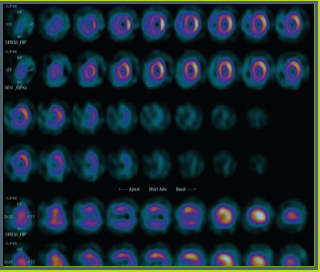

Ecocardiograma tridimensional demonstra comunicação

interatrial ampla na região da fossa oval do septo atrial.